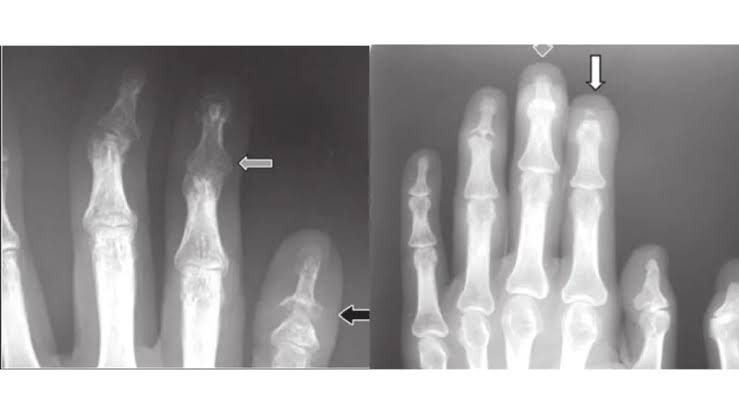

1️⃣ Pencil-in-Cup Deformity 🖊️🥤

🩻 Marginal erosion of proximal & distal phalanges → classic interlocking appearance

🟠 Seen in: Psoriatic arthritis

📌 Common in DIP joints, can progress to arthritis mutilans Image